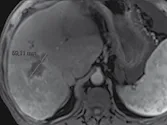

Figure 7. Carcinome hépatocellulaire traité par sorafénib.

Sur l’examen initial (A), la lésion présente deux compartiments sur cette image d’IRM au temps artériel l’un nécrotique, l’autre qui se rehausse, appelé tumeur « viable ».

B. Mesure selon mRECIST du plus grand diamètre de la lésion viable.

C et D. Après quatre mois de chimiothérapie, le compartiment viable de la tumeur passe de 37 à 24 mm, soit une diminution de 35 %. Il s’agit donc d’une réponse partielle, alors que le volume total de la lésion n’a pas changé.

Selon RECIST 1,1, la réponse aurait été « SD »